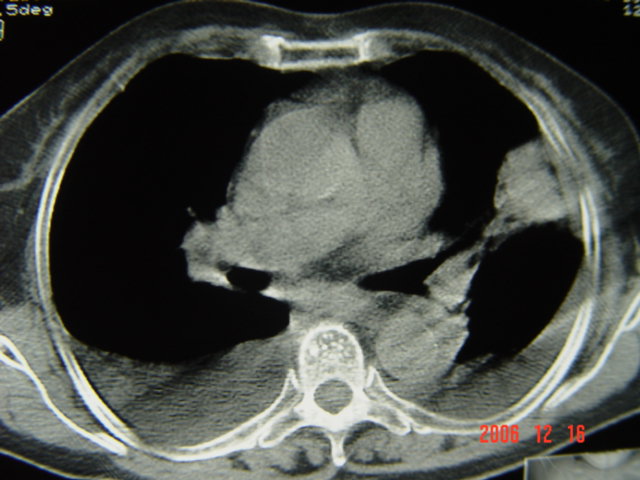

左第八肋腋侧呈膨胀性骨质破坏,内侧见软组织密度肿块。左肺舌段呈楔形实变,基底近胸壁,尖端向肺门。双侧胸壁后缘见新月形水样密度区。

考虑:1、左第8肋骨转移瘤;

2、左肺舌叶肺栓塞可能性大;

3、双侧中量胸腔积液。

考虑1左侧肋骨破坏考虑转移瘤。2左下肺部分肺不张或实变,左肺舌段片团影考虑肺癌可能性大[肺梗塞--往往有明显的胸痛,呼吸急促或困难等表现]。3双侧肺淤血及双侧胸腔积液考虑心功能不全所致可能性大